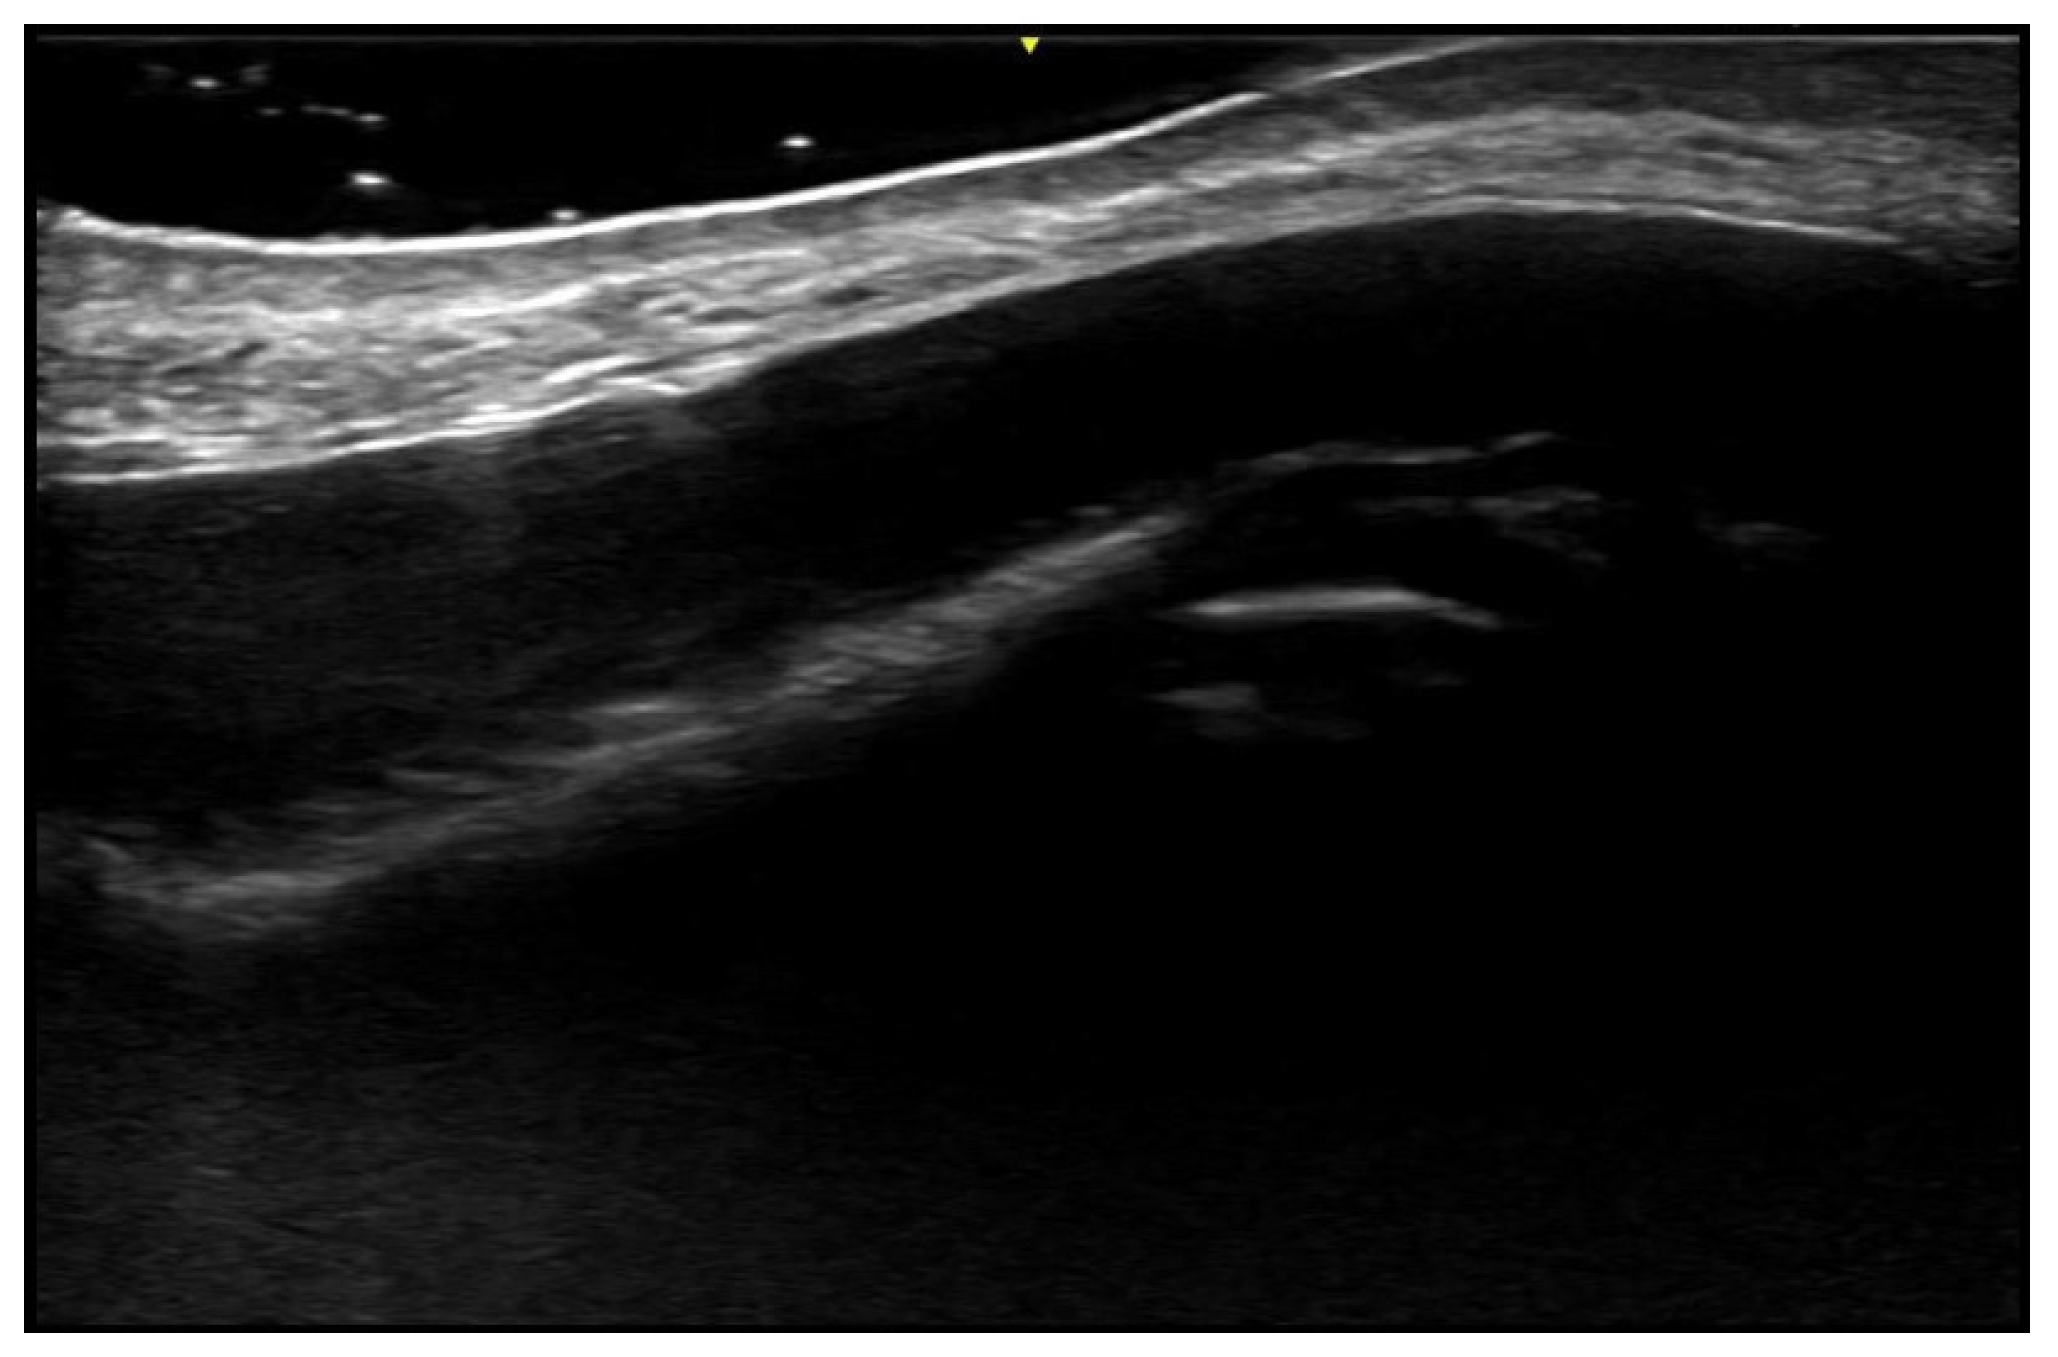

5. Specific Cutaneous Structure and Sites of Skin Disorders